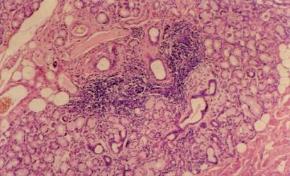

A kis nyálmirigyek daganatának gyanúja esetén excisiós biopsiát végzünk. Sokszor alkalmazzuk a nyálmirigyeket érintő, szisztémás kórképek gyanúja esetén a kis nyálmirigyek incisiós biopsiáját (pl. Sjögren-szindróma, cysticus fibrosis, sarcoidosis, amyloidosis). A kis nyálmirigyek szövettani eltérései jól korrelálnak a nagy nyálmirigyekével, de szemben azok előbbiekben részletezett veszélyeivel, a művelet egyszerű, s a beteg számára alig megterhelő. Az eljárás során nyert anyagból rutin és speciális szövettani vizsgálatokat egyaránt végezhetünk. Általában az alsó ajakból távolítunk el mirigyeket, mivel ez kis nyálmirigyekben a leggazdagabb, egyben a legjobban hozzáférhető és a betegnek is legmegfelelőbb hely, de leírták a bucca és a palatum kis nyálmirigyeinek biopsiáját is. Felületes infiltratiós érzéstelenítés után a szájzug és a középvonal között felületes nyálkahártyametszést ejtünk 1–2 cm hosszban, majd a nyálkahártya és az ajak izomrétege között található nyálmirigyeket tompán preparálva eltávolítjuk. A sebet egy-két csomós öltéssel zárjuk, és műtét után chlorhexidines szájöblögetést rendelünk, az 5 nap múlva elvégzett varratszedés idejéig. Műtéti szövődmények igen ritkán fordulnak elő és elhanyagolhatók (12.7. ábra, 12.8. ábra).

12.7. ábra. Sjögren-szindrómás betegből eltávolított kis nyálmirigy, periductalis lymphocytás fókusszal (HE-festés, 100x)

(átvéve: Dr. Nagy Gábor: Nyálmirigybetegségek, Medicina, Budapest 2000.)